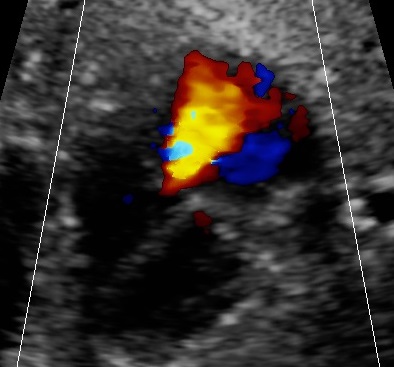

- fetal hypervolemic heart failure (anemia, arrhythmia, tumor, chorangioma, acceptor fetus of the twin-twin transfusion syndrome, pump twin of the TRAP-sequence),

- Doppler velocimetry of the middle cerebral artery to exclude fetal anemia